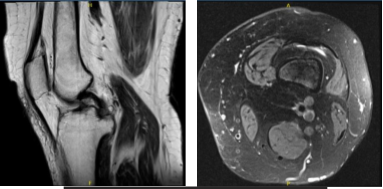

Patient MRI showed significant results. Impression as follows: Vertically oriented tear of the posterior horn medial meniscus extending to the posterior root attachment of the junction of the inner and central thirds.

Shallow fraying of the undersurface of the medial meniscal body. Mild MCL sprain. Mild to moderate chondromalacia patella as well as cartilage loss at the periphery of the lateral trochlea. Joint effusion and thickened medial parapatellar plica.

MRI-3T Left knee non-contrast